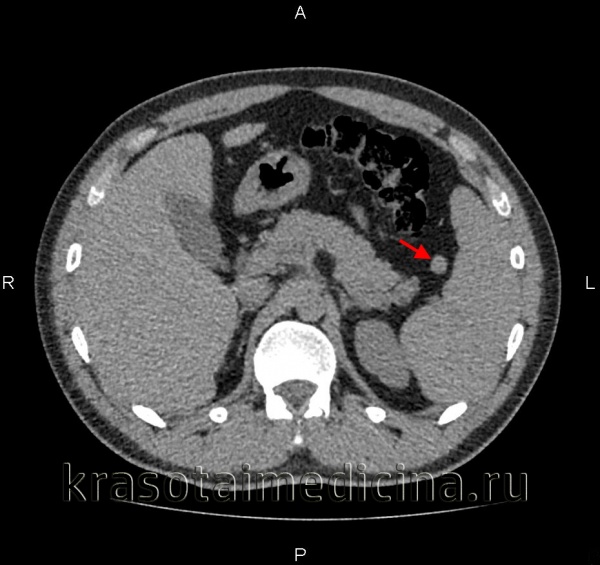

Компьютерная томография брюшной полости. Дополнительная доля селезенки, в соответствии с характеристиками плотности, аналогичной основной селезенке.